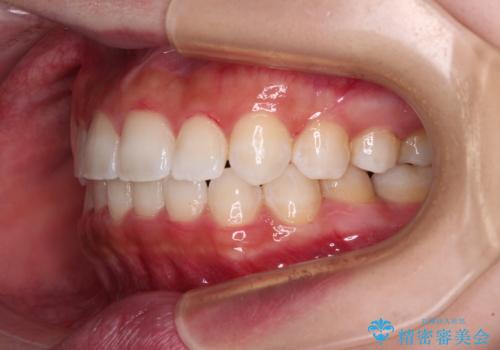

- 八重歯を気にして来院された患者様です。

本来であれば八重歯の隣後方の歯を抜歯するのですが、その後ろの歯が乳歯であり後続永久歯もなかったため、乳歯を抜去することとしました。

前から5番目の乳歯は、後続永久歯である小臼歯と比べて幅径が大きいため、移動に時間がかかりましたが、きれいに仕上げることができました。